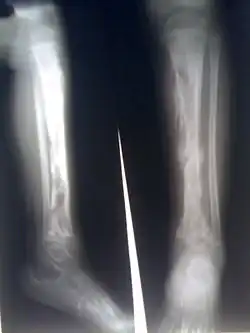

![]() Zapalenie kości piszczelowej u małego dziecka | |

W 85% przypadkach zmiany chorobowe w ostrym zapaleniu kości (pierwotnie występujące zazwyczaj jako zapalenie szpiku) dotyczą kości długich, głównie kości udowych, piszczelowych, ramiennych i promieniowych. U małych dzieci zdarza się również zapalenie kilku kości.